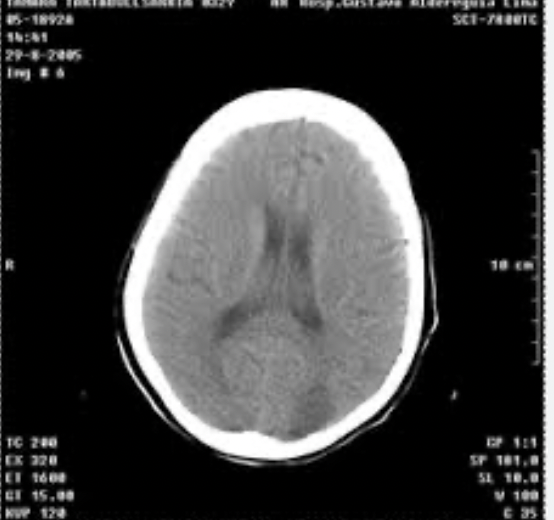

Como se ve el edema cerebral

A

Se ve borramiento de circunvoluciones y cisternas, no se puede diferencia S.gris de blanca, ventrículos, etc

El liquido pasa al intesrticio